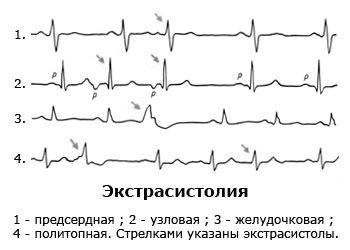

Аритмія найчастіше спостерігається при грудному остеохондрозі, причому ці два захворювання можуть бути пов'язані між собою. Прогресування остеохондрозу призводить до появи в грудних сегментах хребта протрузий і гриж міжхребцевих дисків, здатних викликати компресію нервових закінчень, що мають зв'язок з серцем. У цьому випадку поява аритмії стає досить імовірним.

- Проходження електрокардіографії (звичайне ЕКГ), холтерівського моніторування (добове ЕКГ) і ехокардіографії.